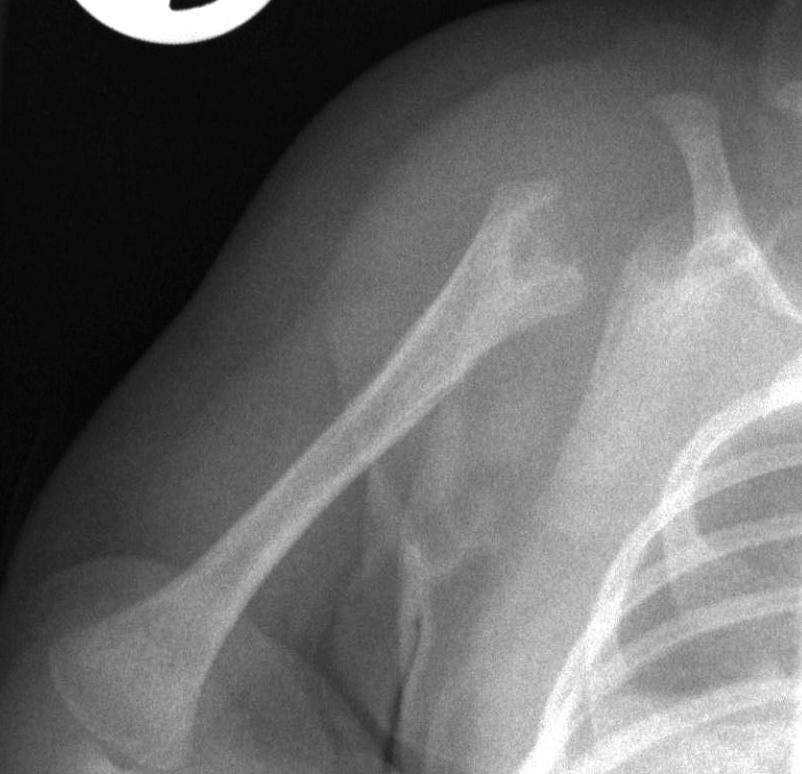

37.a.

Image

37.b.

37.c.

37.d.

37. a-d) X-ray of the right humerus. a. Rarefaction in the proximal-medial part of metaphysis of the right humerus – early osteomyelitis. b. Two weeks after the lytic area has grown. c. 1 month later sclerotic regeneration has begun. d. 4 months after almost complete healing. Osteomyelitis, infant.